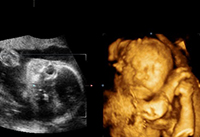

現(xiàn)在有許多媽媽說通過四維彩超可以查看男女,說是四維彩超里男女寶寶圖片是有區(qū)別的,為了證實(shí)這一切的真假性,下面,趕緊隨本文一起來看看,四維男女寶寶區(qū)別圖有何不同,及如何利用...